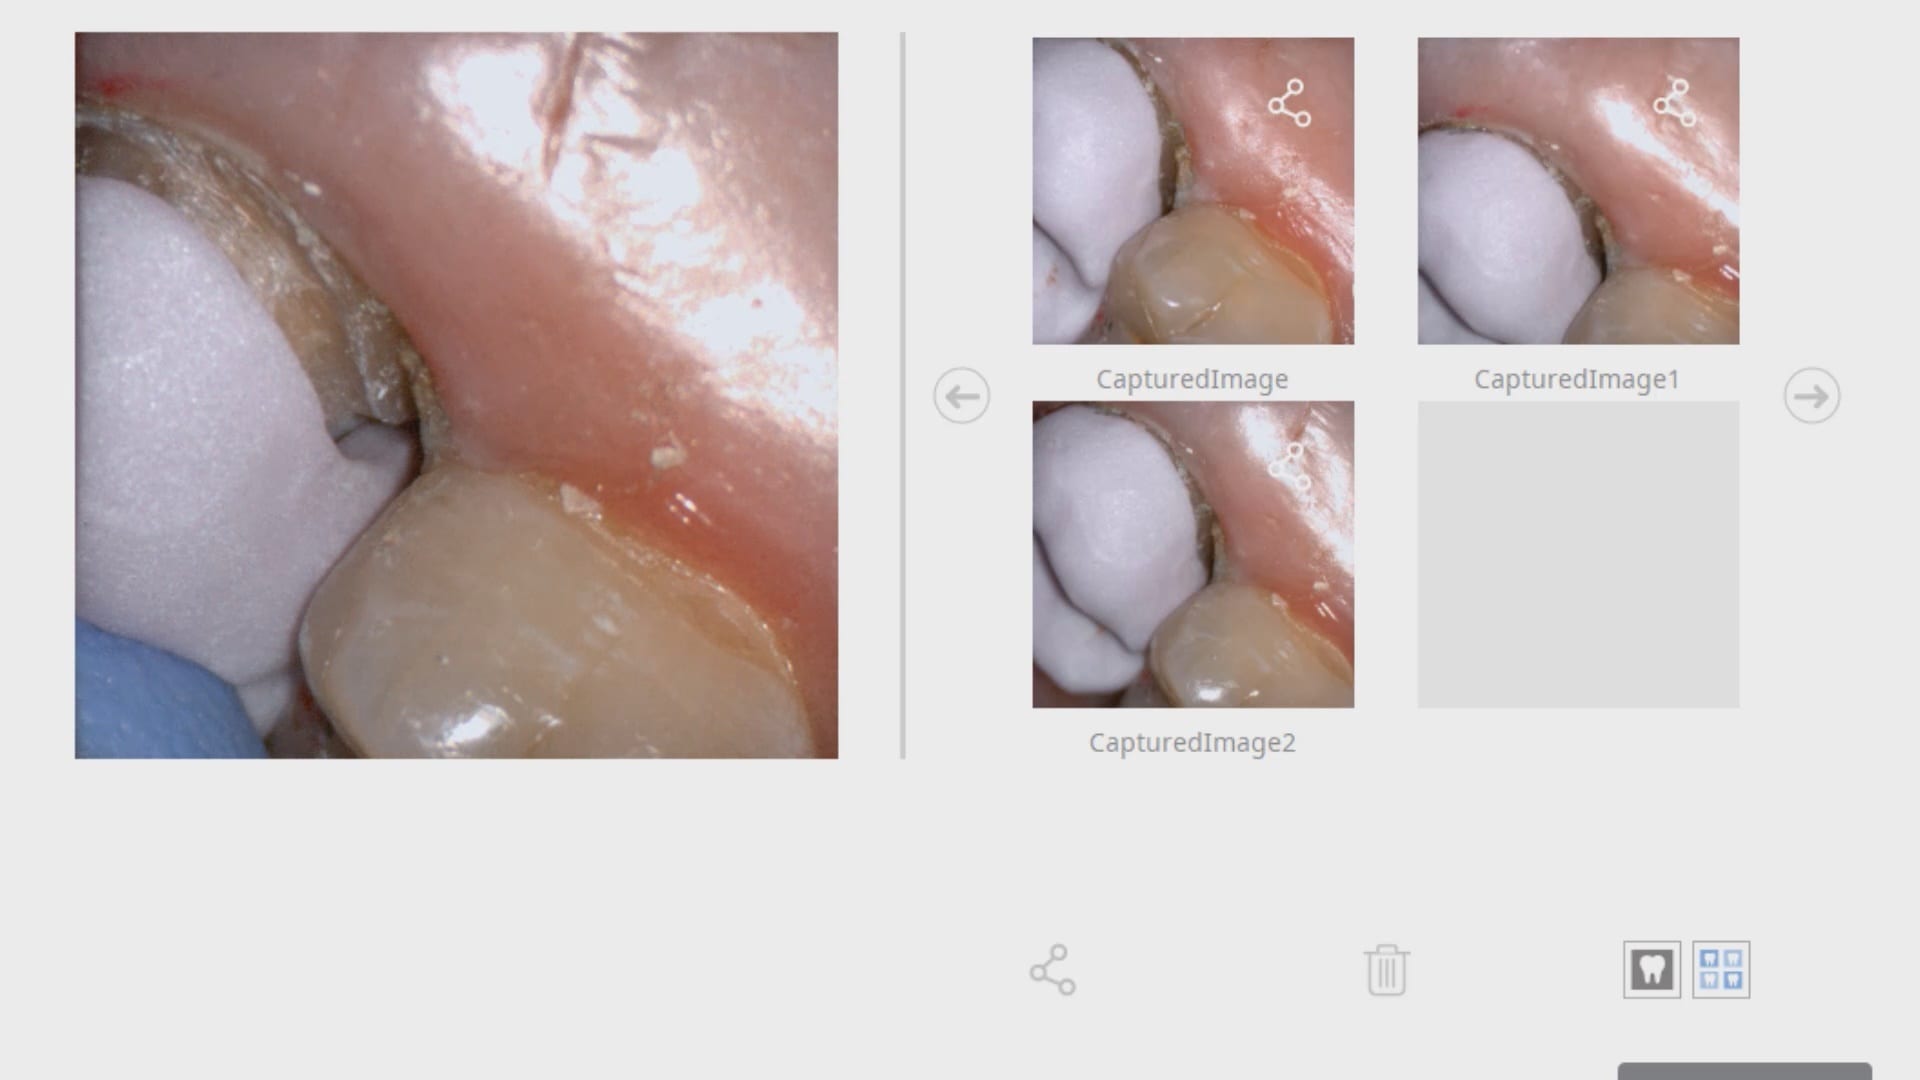

With analog dental impressions, it is imparative to separate the gum tissue from tooth structure and to create a trough for flash for dye work. This is not the case with the intra-oral scanner by Medit. All you need to do is displace the tissue so you have a clear line of site to the margins, and you just need to be flush. You don’t need flash like you do with stone work